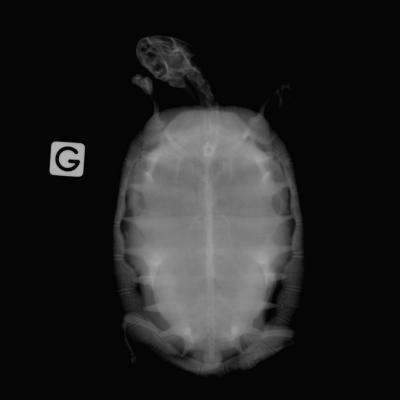

Tortue

Oeufs de Tortue